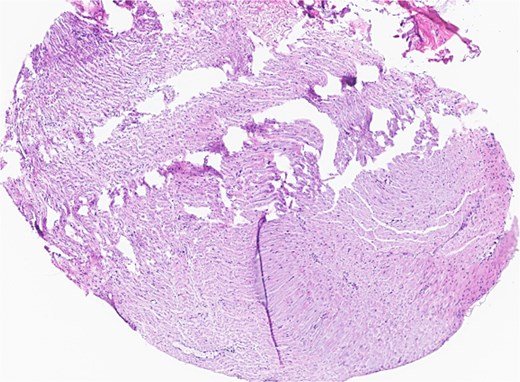

Subsequent surgery included left partial auriculectomy, wide local excision, and lateral temporal bone resection. Pathology revealed lymphatic invasion (LVI), perineural invasion (PNI), and facial nerve and mastoid bone involvement (Figs 4 and 5). CLL-fluorescence in situ hybridization (FISH) revealed 13q deletion; Immunoglobulin Heavy Chain gene (IGH) somatic hypermutation analysis identified IGHV3–23*01 rearrangement (mutated level 5.7%). Due to prior radiation, six cycles of cemiplimab were planned. A follow-up PET-CT scan showed enlarged, FDG-avid cervical lymph nodes and soft tissue nodularity beneath the posterior margin of the graft.

Facial nerve, left, proximal margin, biopsy: focally involved by invasive SCC.

Ear, left, auriculectomy: invasive moderately differentiated SCC, forming a poorly demarcated infiltrating dominant mass, ~5.5 cm in size and 2 cm in depth of invasion; extensive nerve invasion and focal lymphovascular invasion.